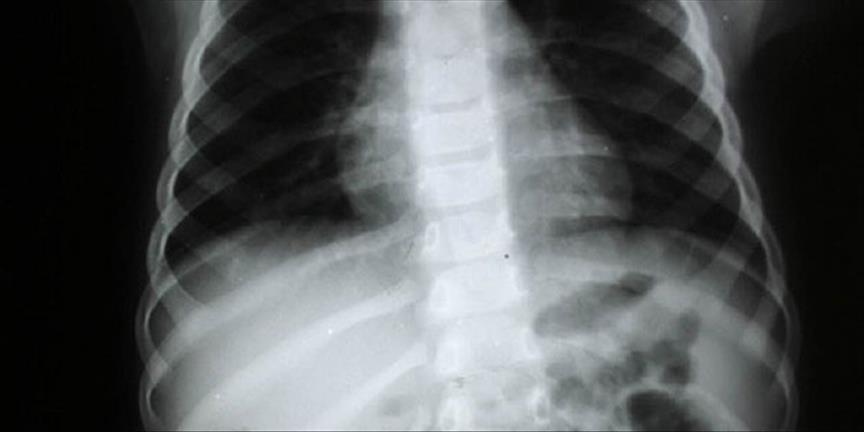

Dünyanın birçok ülkesinde uygulanan ve Türkiye'de yeni kullanılmaya başlanan dört boyutlu analiz yöntemi, omurga eğriliğinin (skolyoz) 4 saniyede tespit edilmesini sağlıyor. Konuyla ilgili AA muhabirine açıklama yapan Kocaeli Romatem Fizik Tedavi ve Rehabilitasyon Hastanesi Başhekimi uzman doktor Ertunga Öney, skolyozun omurganın orta hattan yana doğru olan eğriliklerini tanımladığını söyledi.

Hastalığın tanısının muayene ve görüntüleme yöntemleri ile konduğunu, en sık kullanılan yöntemin de ''x'' ışınları olduğunu, ancak yeni yöntemin radyasyon içermediğini dile getiren Öney, konuşmasını şöyle sürdürdü:

''Bu yöntemin tedavideki önemi, hastanın deformite bölgelerinin tespiti ve tedavideki ilerlemenin gözlenmesini zararsız bir şekilde ölçümlendirilebilmesidir. 'x' ışını olmadığı için de ölçüm istendiği kadar tekrar edilebiliyor. Özellikle skolyozun daha çok çocukluk çağında görülen bir hastalık olduğu düşünülürse radyasyon içermemesi önem içermektedir. ''